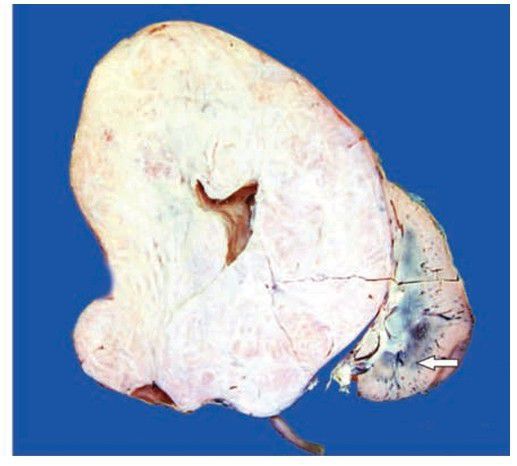

Nephroblastoma (Wilms’ tumour). The kidney is enlarged and has ovoid and nodular appearance. The sectioned surface shows replacement of almost whole kidney by the tumour leaving a thin strip of compressed renal tissue at lower end (arrow). Cut section of the tumour is gray white, fleshy and has small areas of haemorrhages and necrosis.